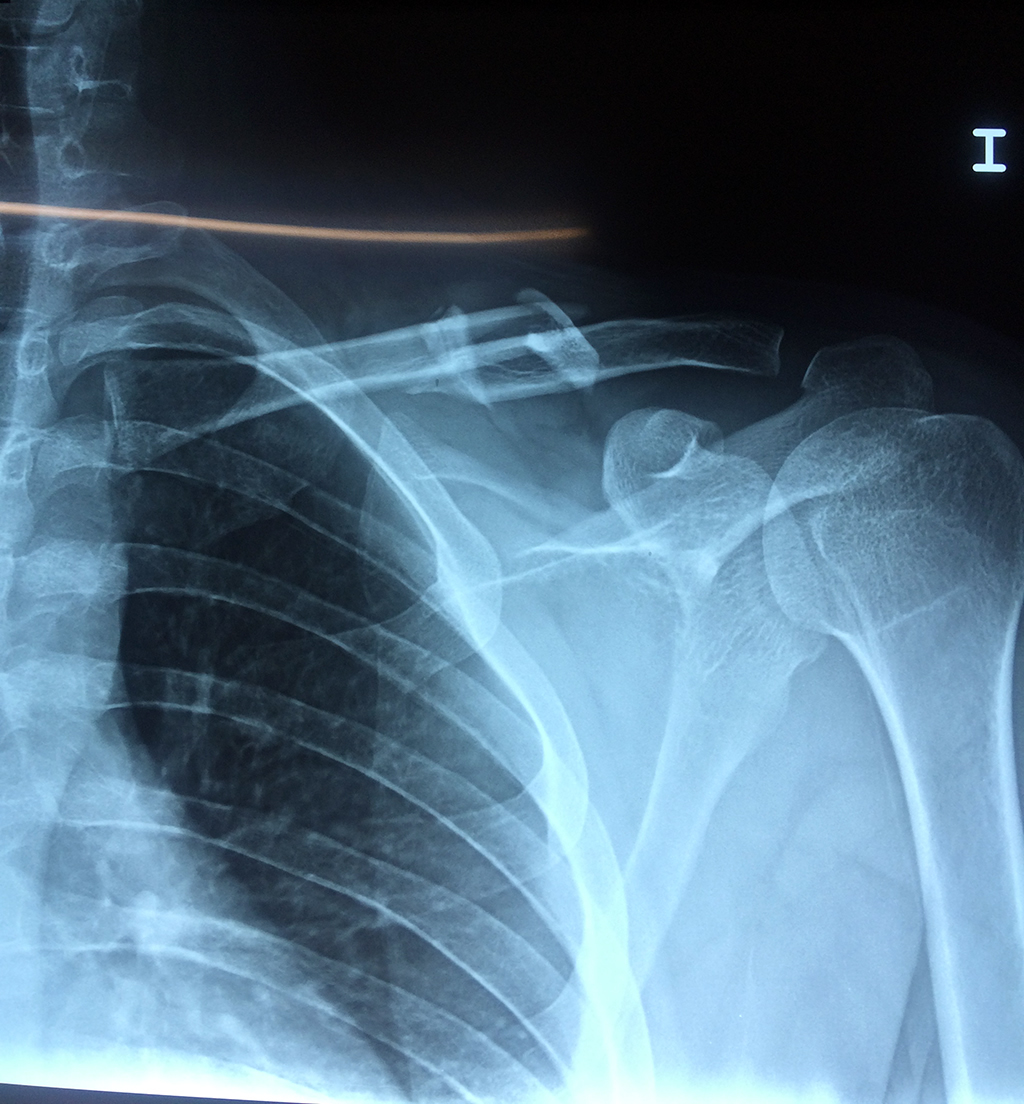

Cirugías de Codos - Clavícula

La clavícula es un hueso largo, con forma de "S" itálica, situado en la parte anterosuperior del tórax. Junto con la escápula forman la cintura escapular. Se puede palpar por toda su longitud y se extiende del esternón al acromion de la escápula, siguiendo una dirección oblicua lateral y posterior.

Se considera el único medio de unión entre el miembro superior y el tórax. A pesar de su aspecto, similar al de un hueso largo, posee una estructura semejante a la de un hueso plano, ya que carece de epífisis y de diáfisis, lo que la harían entrar dentro de la clasificación de hueso largo. Carece de un canal medular propiamente dicho.